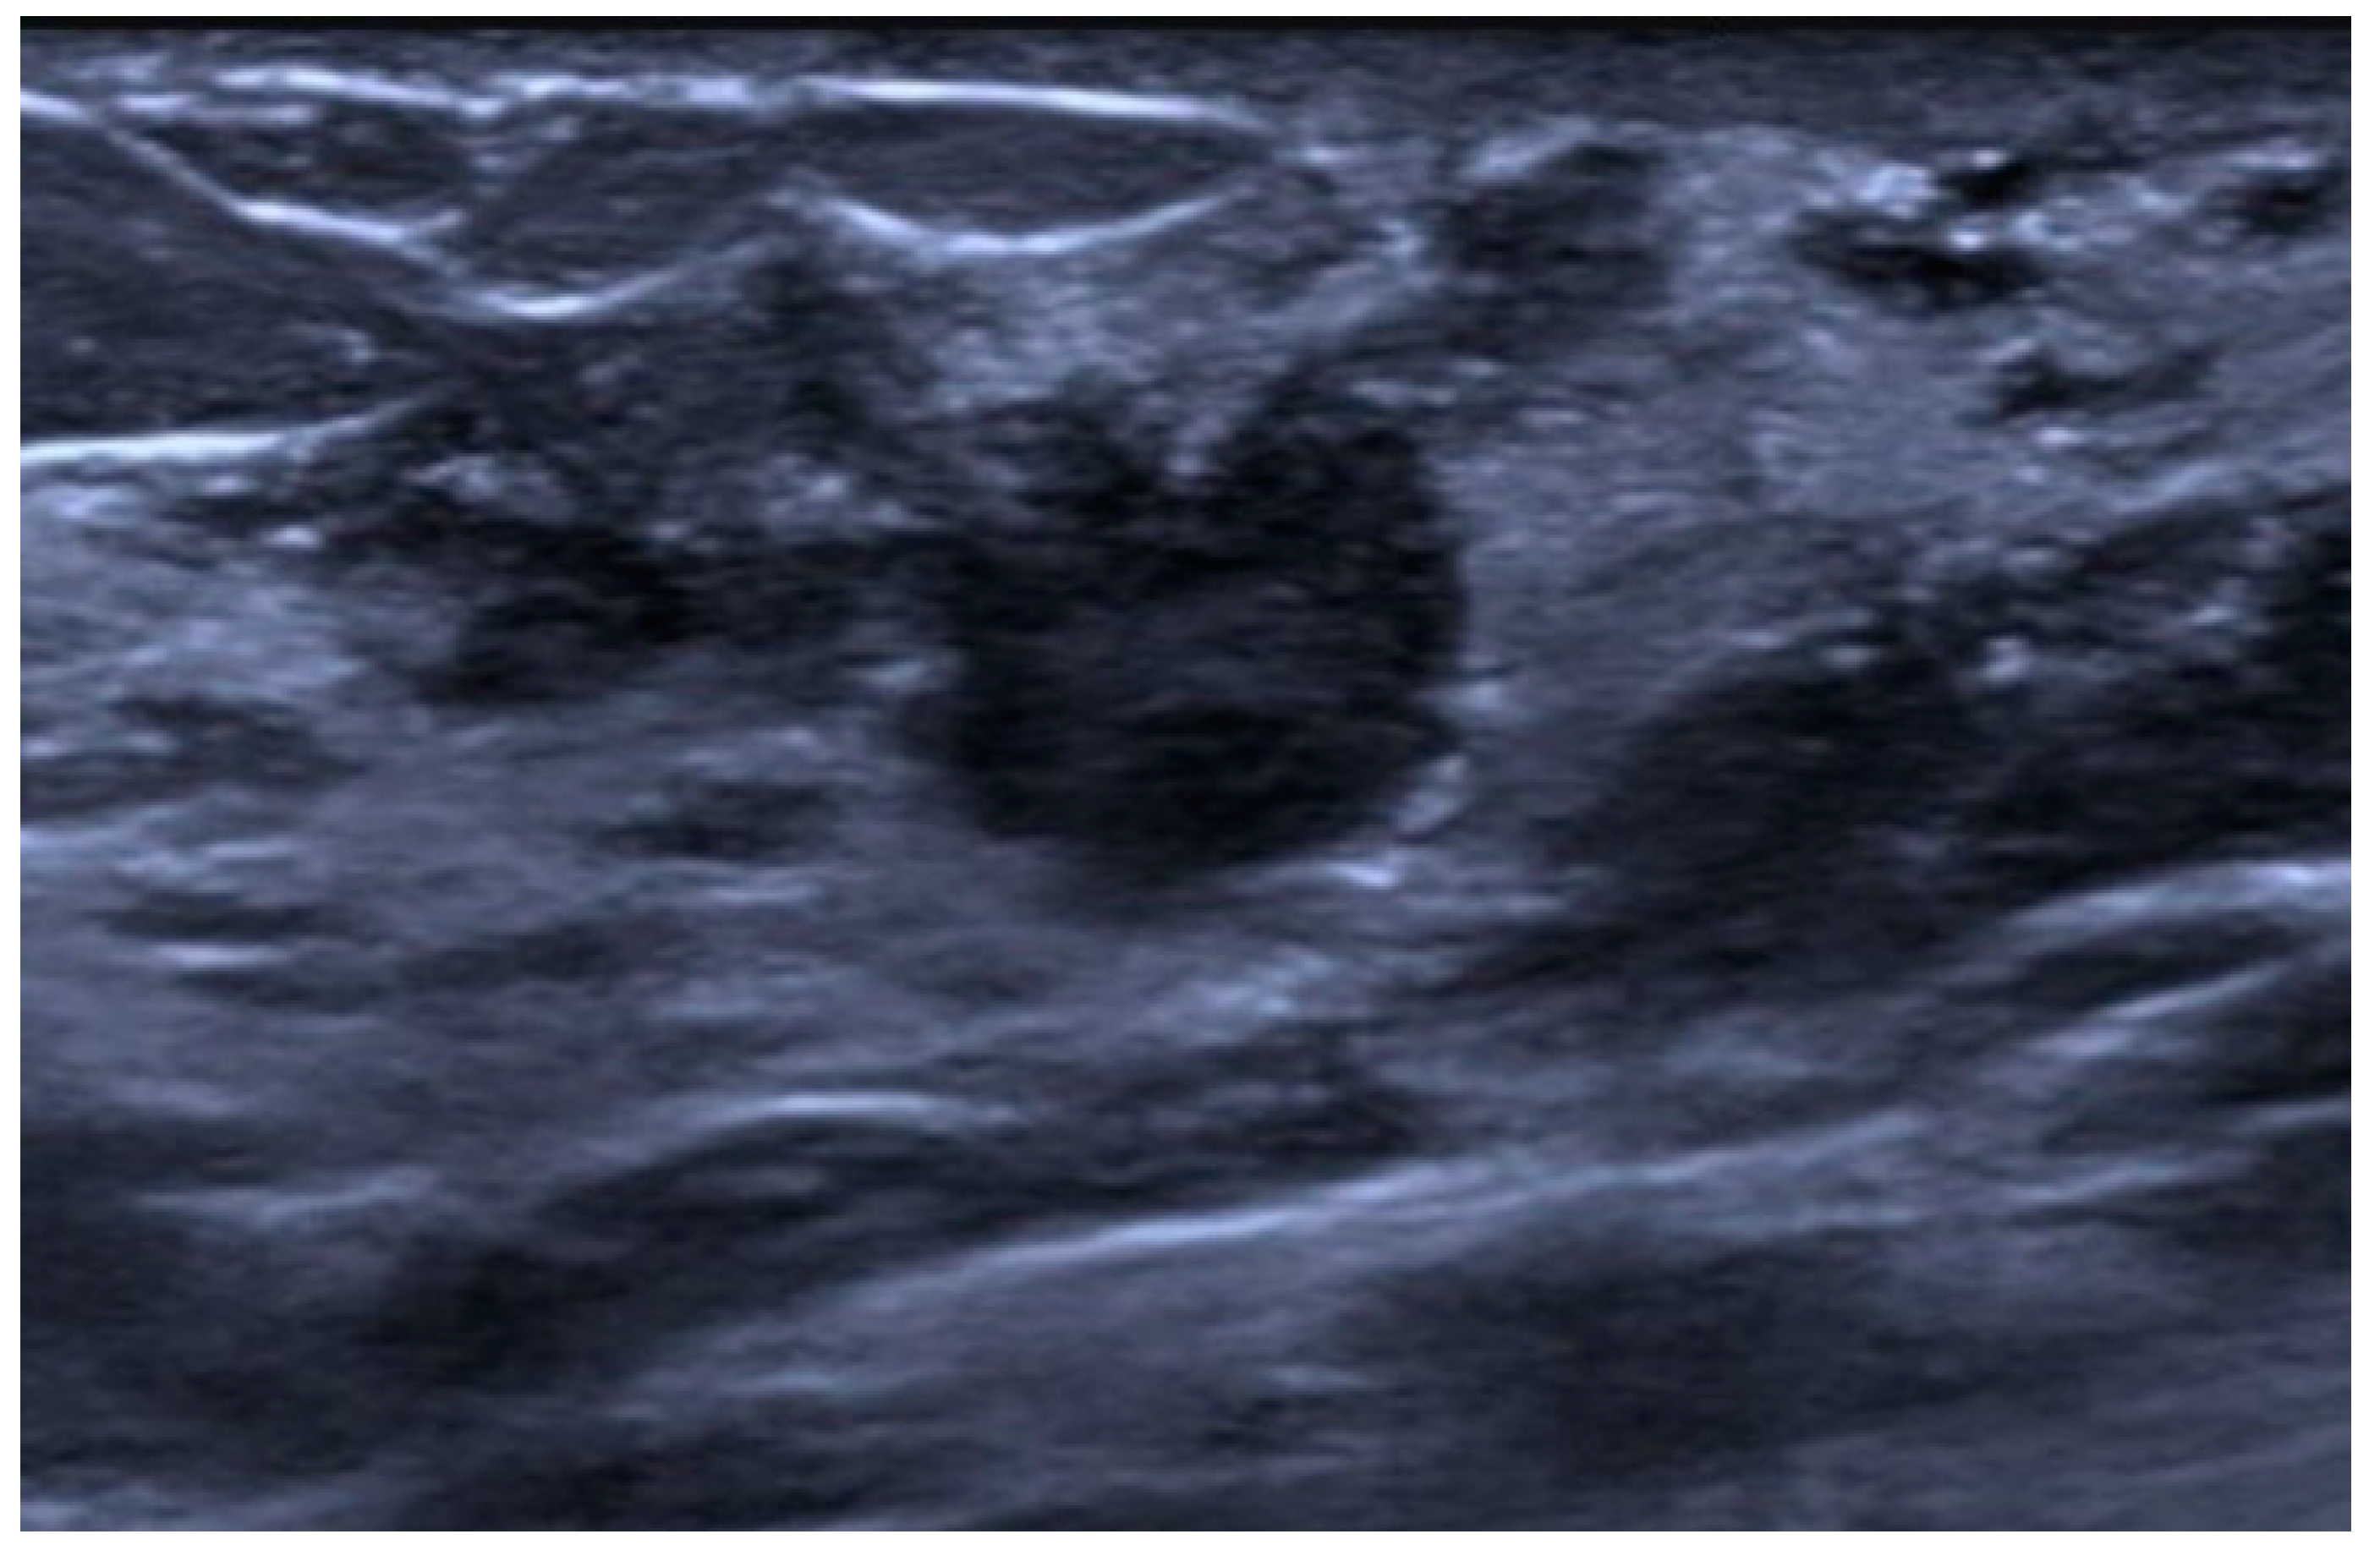

10. Metaplastic